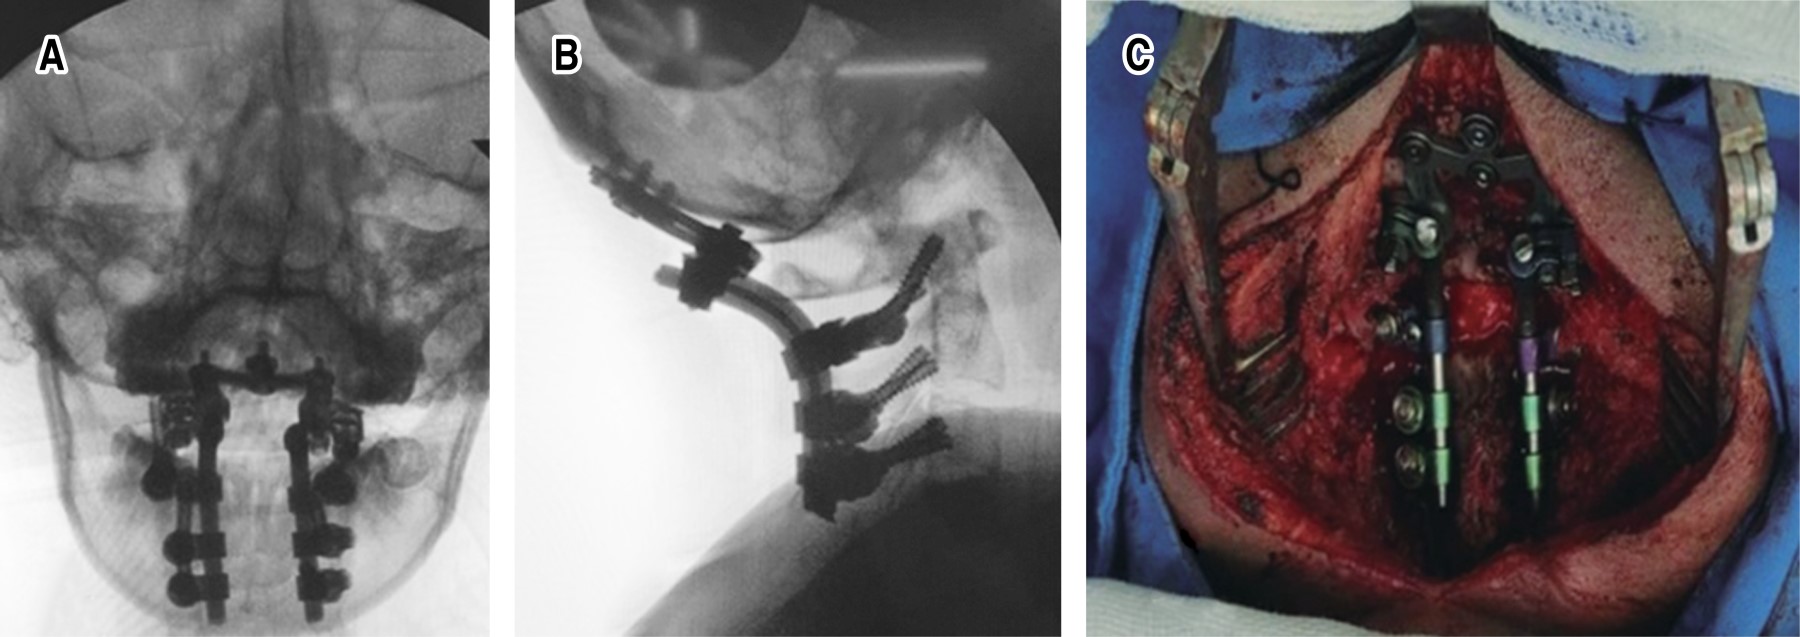

Introduction: injuries to the craniocervical junction with instability secondary to trauma are rare; with complications with a high mortality rate. When both lesions are present; the patient's prognosis for survival and recovery is usually very poor. Surgical treatment for reconstruction of the occipitocervical junction are complex and uncommon procedures; in most cases they have been studied in the treatment of degenerative and rheumatic pathologies. Clinical case: 27-year-old female patient, with combined occipitoatloid-atlantoaxial instability secondary to an accident in a motorcycle-type vehicle; which has multiple injuries. Diagnosis: clinic with neurological deficit; radiological studies of trauma, and axial tomography of the skull and spine, where data of instability at the C0-C1 and C1-C2 levels are evident. Interventions: multidisciplinary management and subsequently occipitocervical reduction and fixation with Harms technique of the injuries due to traumatic vertebral instability; C0-C1, C1-C2 and C2-C3. Follow-up: 9 months after the intervention, with adequate clinical evolution. Conclusions: although there are few publications and guides on the diagnosis, ideal moment of intervention and optimal stabilization method in cases of instability due to trauma, we recommend a multidisciplinary approach. Early diagnosis and treatment directly influence the final prognosis and quality of life of these patients.

Figure 4